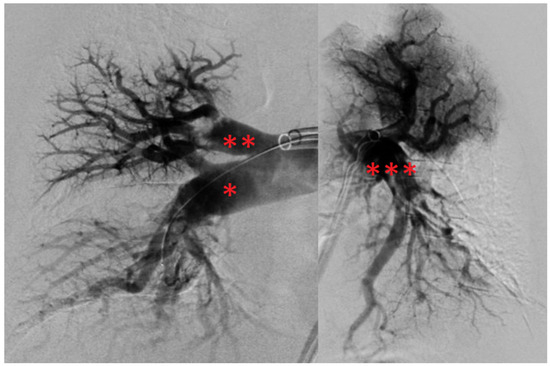

Elevation of high-sensitivity cardiac troponin T (43 ng/L) and NT-pro-BNP levels (3538 ng/L), as well as the hypoxemic respiratory failure found in the arterial blood gases (pO2: 67 mm Hg, pCO2: 24 mm Hg), underpinned the diagnosis. Pulmonary Embolism Severity Index (PESI) and simplified PESI (sPESI) scores were calculated to be 96 and 1, respectively [21,22]. From his PESI score, the patient was categorized as class III, revealing a moderate 30-day mortality risk (approximately 3–7%) [1,21]. Clinically, the patient was classified as intermediate–high risk [1]. Moreover, a DVT in the medial segment of the left posterior tibial vein was detected by compression ultrasonography. Based on this, he was anticoagulated therapeutically with unfractionated heparin by use of a perfusor. Interventional radiology was contacted with the request for endovascular mechanical thrombectomy, and the patient was transferred to the angiography suite. After bilateral ultrasound-guided access to the common femoral veins, thrombus in the pelvic veins and the inferior vena cava were ruled out using phlebography. The pulmonary trunk was selected using a 5F pigtail catheter, pulmonary artery pressures (PAP) were measured, and digital subtraction angiography (DSA) was performed (Figure 3). PAP measurements revealed elevated pressures with a mean PAP (mPAP) of 42 mm Hg. DSA confirmed CT findings with filling defects and a lack of contrasting of pulmonary parenchyma, especially in the right lower lobe. A stiff guidewire was navigated into the right lower lobe pulmonary artery. The 24F endovascular mechanical thrombectomy device (FlowTriever System) was advanced into the right lower lobar artery. Abundant embolic material was retrieved by repeated aspiration thrombectomy. In the left lung, initial attempts failed. By switching to a FlowTriever catheter containing disks for mechanical thrombus maceration and subsequently continuing aspiration thrombectomy, abundant embolic material was extracted from the left pulmonary arteries as well, particularly from the left lower lobar artery. The thrombi recovered from the pulmonary arteries are shown in Figure 4. Subsequently, a control DSA revealed open and well-perfused pulmonary arteries with only minimal residual thrombotic material (Figure 5). The mPAP immediately decreased by 28 mm Hg from an initial 42 to 14 mm Hg (systolic pulmonary artery pressure (sPAP): 65 → 28 mm Hg; diastolic pulmonary artery pressure: 29 → 6 mm Hg). After the intervention, the patient was hemodynamically stable and free of complaints, only experiencing slight remaining exertional dyspnea. From the patient’s perspective, the intervention was well tolerated. To minimize blood loss during the procedure, an autotransfusion system was used (FlowSaver, Inari Medical, Irvine, CA, USA). Moreover, it was carried out without complications, apart from a small postinterventional venous bleed at the access site in the right groin, which was managed by manual compression.

Figure 3. DSA findings before endovascular mechanical thrombectomy. Annotation: right interlobar artery (*) appears truncated with no parenchymal contrasting of the right lower lobe. There are significant filling defects in the right superior trunk (**), the left interlobar artery (***) and the left apical segmental arteries, also with a lack of contrasting of the corresponding pulmonary parenchyma. DSA, digital subtraction angiography.

Figure 5. DSA findings after endovascular mechanical thrombectomy. Annotation: Near-complete contrasting of the right interlobar artery (*), the right superior trunk (**), left interlobar artery (***) and left apical segmental arteries with only small remaining filling defects corresponding to small residual thrombi. DSA, digital subtraction angiography.